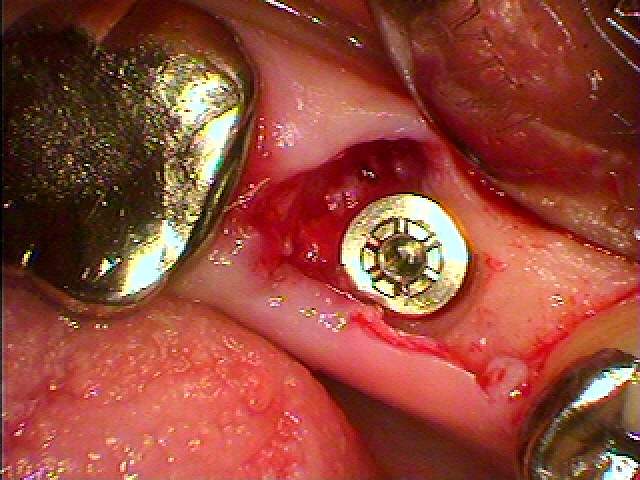

左下の奥歯のインプラント埋入|お知らせ |広島市安佐南区の歯科医院 左下の奥歯のインプラント埋入 トップ お知らせ・ブログ お知らせ 左下の奥歯のインプラント埋入 左下の奥歯のインプラント埋入 左下の6番ヘミセクション このクラウンが揺れてきました 骨吸収が認められます 割れているため抜歯となりました 抜歯しました 埋入していきました 補填材を入れ縫合して終了です このように埋入しています Web診療予約 初めての方へ 選ばれ続ける理由 院内設備について 歯が痛いしみる一般歯科 歯がぐらぐらする歯周病 健康な歯を保ちたい予防歯科 子供の虫歯予防をしたい小児歯科 銀歯をセラミックに審美歯科 白い歯を目指しませんか?ホワイトニング 矯正専門医がいるので安心矯正歯科 抜けた歯を補いたいインプラント・入れ歯 医院案内 スタッフ紹介 メリィハウス歯科クリニックオフィシャルホームページ ラベンダー歯科クリニックオフィシャルホームページ お知らせ・ブログ ホーム 診療科目 一般歯科 歯周病治療 予防治療 小児歯科 審美治療 ホワイトニング 矯正歯科 入れ歯・インプラント マウスピース矯正 初めての方へ 院長・スタッフ 設備紹介 医院案内・アクセス メニューを閉じる